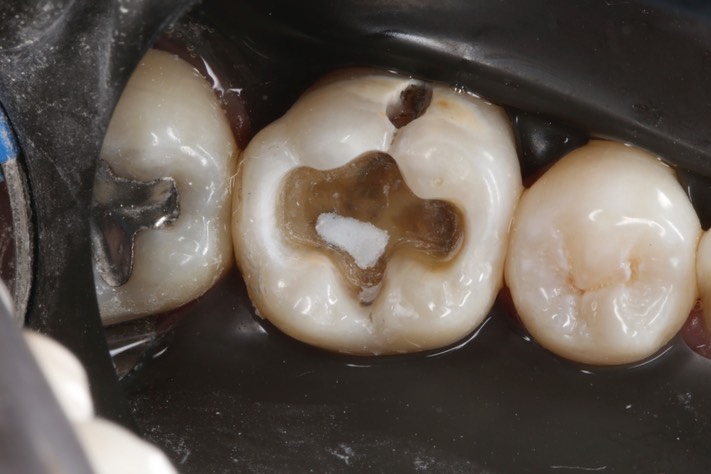

Wes Sato #30 prep